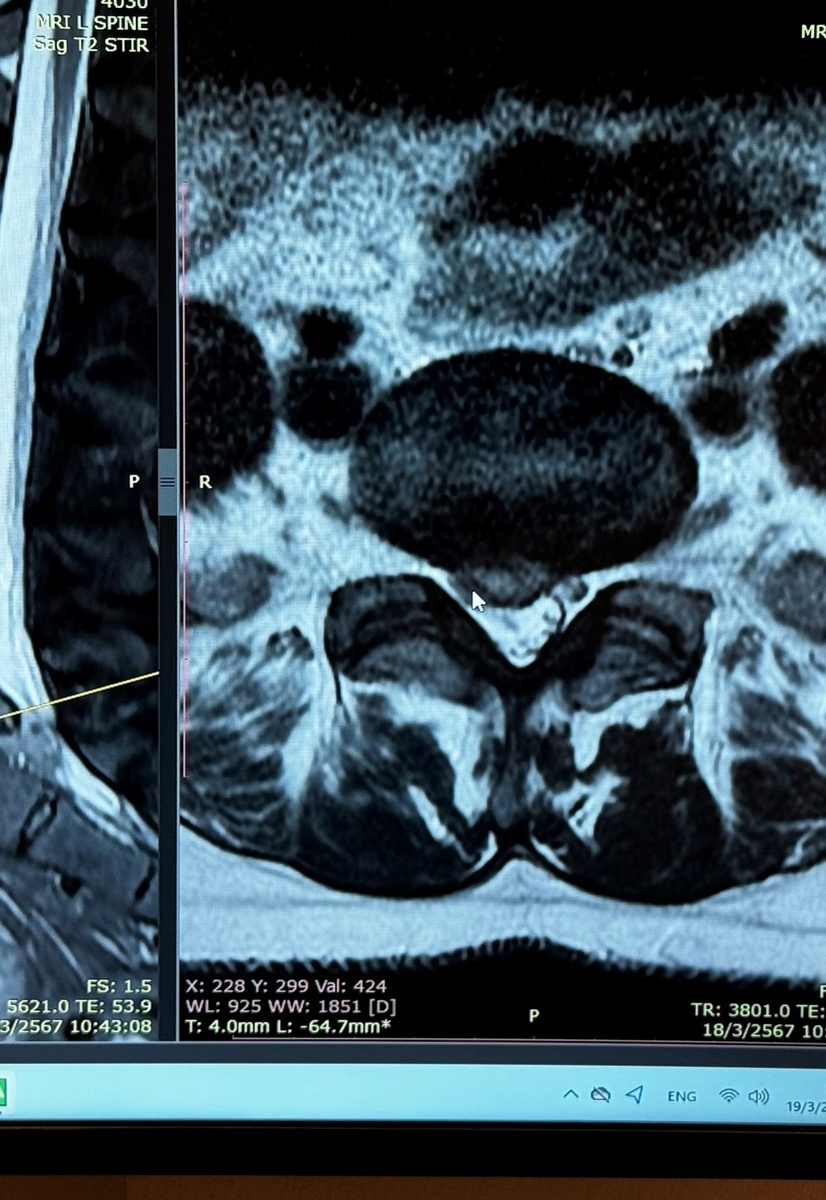

По возвращении я нахожу клинику физиотерапии и реабилитации. Они мне оформляют письмо в Бангкок Госпиталь, чтобы снизить стоимость МРТ. Без этого письма, стоимость диагностики 16000 батов(38400 рублей). Медицина в Таиланде очень дорогая! Поэтому, страховка – мастхэв. С письмом сумма выходит в два раза меньше. По результатам обследования, произошло секвестрирование(разрыв) той самой грыжи. Ее содержимое вышло в межпозвоночное пространство и дальше. Я сейчас могу привирать термины, описываю своими словами, уж простите. В общем, насколько я поняла, в момент вертикального давления массажистки произошла компрессия дисков и хлоп! грыжа вскрылась. Было сужено пространство и сильное давление на нервные корешки.

Дальше у меня была эпопея на пол года по восстановлению. Я прошла два курса лазера, направленного на резорбцию секвестра плюс иголки, плюс гимнастика в бассейне. Через пару недель после начала уже после окончания приема обезболов, боль начала спадать. Я по-прежнему хромала. Стопа не работала, икроножная тоже. Примерно через месяц стало получаться в воде подняться на мысок. На суше никак. Только месяцев через 8 работы на тренажерах я смогла оторвать пятку на пару сантиметров от пола. После того, как завершилась терапия, болей уже не было. Я сделала проверочное МРТ, которое подтвердило полное исчезновение грыжи(почти полное) и расширение пространства для нервов. Дальше работала уже сама.